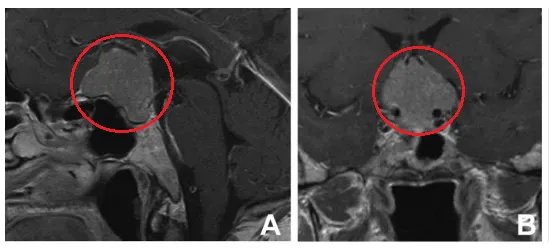

▼T1加权增强矢状面(A)和冠状面(B)磁共振成像显示鞍结节脑膜瘤。

人到中老年,视力变差很容易就会想到是“老花眼”,从而被忽视。61岁的Emmy,初期视力变差时就以为自己是“老花眼”,一直没有治疗。没想到视野也出现缺损,因为还能够维持正常地生活。Emmy仍没怀疑过自己视力变差的原因,没想到然后竟视力丧失。医院检查,头颅磁共振提示:鞍结节脑膜瘤。

不开颅从眉弓入路取瘤靠谱吗?